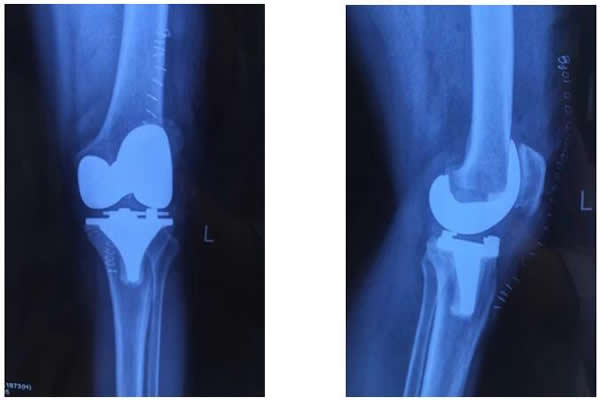

術(shù)前,骨科主任張富軍、主治醫(yī)師張浩為患者制定了嚴(yán)格的治療方案,經(jīng)過2周的術(shù)前準(zhǔn)備感染指標(biāo)降至正常,于2017年1月13日在手術(shù)室、麻醉科等相關(guān)科室的周密配合下,由張富軍主任、張浩主治醫(yī)師、何鵬主治醫(yī)師、裴海波醫(yī)師為白奶奶進(jìn)行同期雙側(cè)人工膝關(guān)節(jié)表面置換手術(shù),麻醉由龐曉紅主任、劉文雄醫(yī)師擔(dān)任,手術(shù)順利,手術(shù)歷時(shí)2.5小時(shí),術(shù)后恢復(fù)滿意,術(shù)后第1天白奶奶已能下床行走,術(shù)后第6天行走出院,白奶奶對手術(shù)效果非常滿意并讓家人為骨科送來了錦旗表示感謝。

目前,西電醫(yī)院骨科治療骨關(guān)節(jié)炎進(jìn)行人工關(guān)節(jié)置換手術(shù)經(jīng)驗(yàn)巳經(jīng)非常成熟,以往對于七十周歲以上的患者往往一次只做一側(cè)。隨著我國老齡人口的不斷增加,高齡患者會(huì)越來越多,骨關(guān)節(jié)炎疾病影響老人生活質(zhì)量,對骨科醫(yī)生也是個(gè)新挑戰(zhàn)。近年來隨著骨科關(guān)節(jié)置換技術(shù)的不斷提高,關(guān)節(jié)置換手術(shù)的時(shí)間也大大縮短;同時(shí)對相應(yīng)的并發(fā)癥也有了一定的預(yù)防和處理能力,如氨甲環(huán)酸和利伐沙班等藥物的合理使用,在大幅度減少手術(shù)出血的同時(shí)也將深靜脈血栓形成的風(fēng)險(xiǎn)降到最低。采用國際快速康復(fù)理念,通過圍手術(shù)期制定個(gè)體化的鎮(zhèn)痛方案和康復(fù)鍛煉計(jì)劃,幫助患者在基本無痛的良好體驗(yàn)下盡快恢復(fù)關(guān)節(jié)功能。